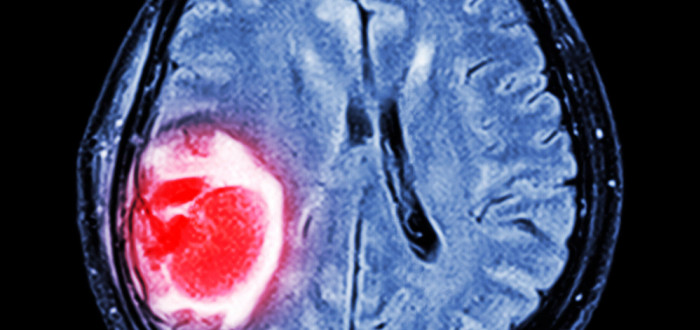

Zhoubné nádory mozku jsou pro širokou veřejnost stále poměrně neznámé. Přitom jde o krajně nebezpečné onemocnění. Jsou velmi agresivní a člověk si s nimi často nedokáže poradit. Pravděpodobnost na uzdravení je u některých skupin nádorů bohužel stále velmi malá.

Zhoubný novotvar mozku označuje nějaké nádorové onemocnění, které představuje závažný problém pro pacienta i jeho okolí. Proces léčby je velmi náročný a často vyžaduje i odbornou psychologickou podporu. Daná terapie pak záleží na mnoha faktorech, běžně se však přistupuje k operaci, ozařování, chemoterapii nebo symptomatické léčbě.

„Pro nádory postihující mozek a mozkové obaly je příznačné, že rostou v uzavřeném prostoru lebky. Právě proto mohou být i typicky benigní či nezhoubné nádory smrtelně nebezpečné kvůli nárůstu nitrolebečního tlaku. Pokud to umístění nádoru a zdravotní stav pacienta dovoluje, přistupuje se primárně k operačnímu řešení,“ vysvětluje MUDr. Kristina Slavíková, revizní lékařka VoZP.

Konkrétní prognóza se však podle lékařky liší případ od případu. „Některé nádory mozku jsou díky moderním přístupům léčitelné a pacient má šanci na úplné zotavení. I přes pokrok onkologie ovšem stále existují skupiny nádorů, u kterých je pravděpodobnost uzdravení malá. Léčba ale může pacientovi prodloužit život, nebo alespoň zmírnit příznaky.“

Příčiny nejsou známé

Mezi příznaky onemocnění patří podle lékařky například bolest hlavy, která je velmi intenzivní a horší při probuzení, ale i náhlé nevolnosti, zhoršení zraku a dalších smyslů, problémy s mluvením či motorikou. „Tyto zhoubné novotvary patří mezi nejagresivnější a nejnebezpečnější pro lidské zdraví, jejich počty se meziročně zvyšují. Jako u všech typů rakoviny je i u nádorů mozku důležitá hlavně včasná detekce. Pokud máte jakékoli neurologické potíže, informujte svého praktického lékaře,“ apeluje MUDr. Slavíková.